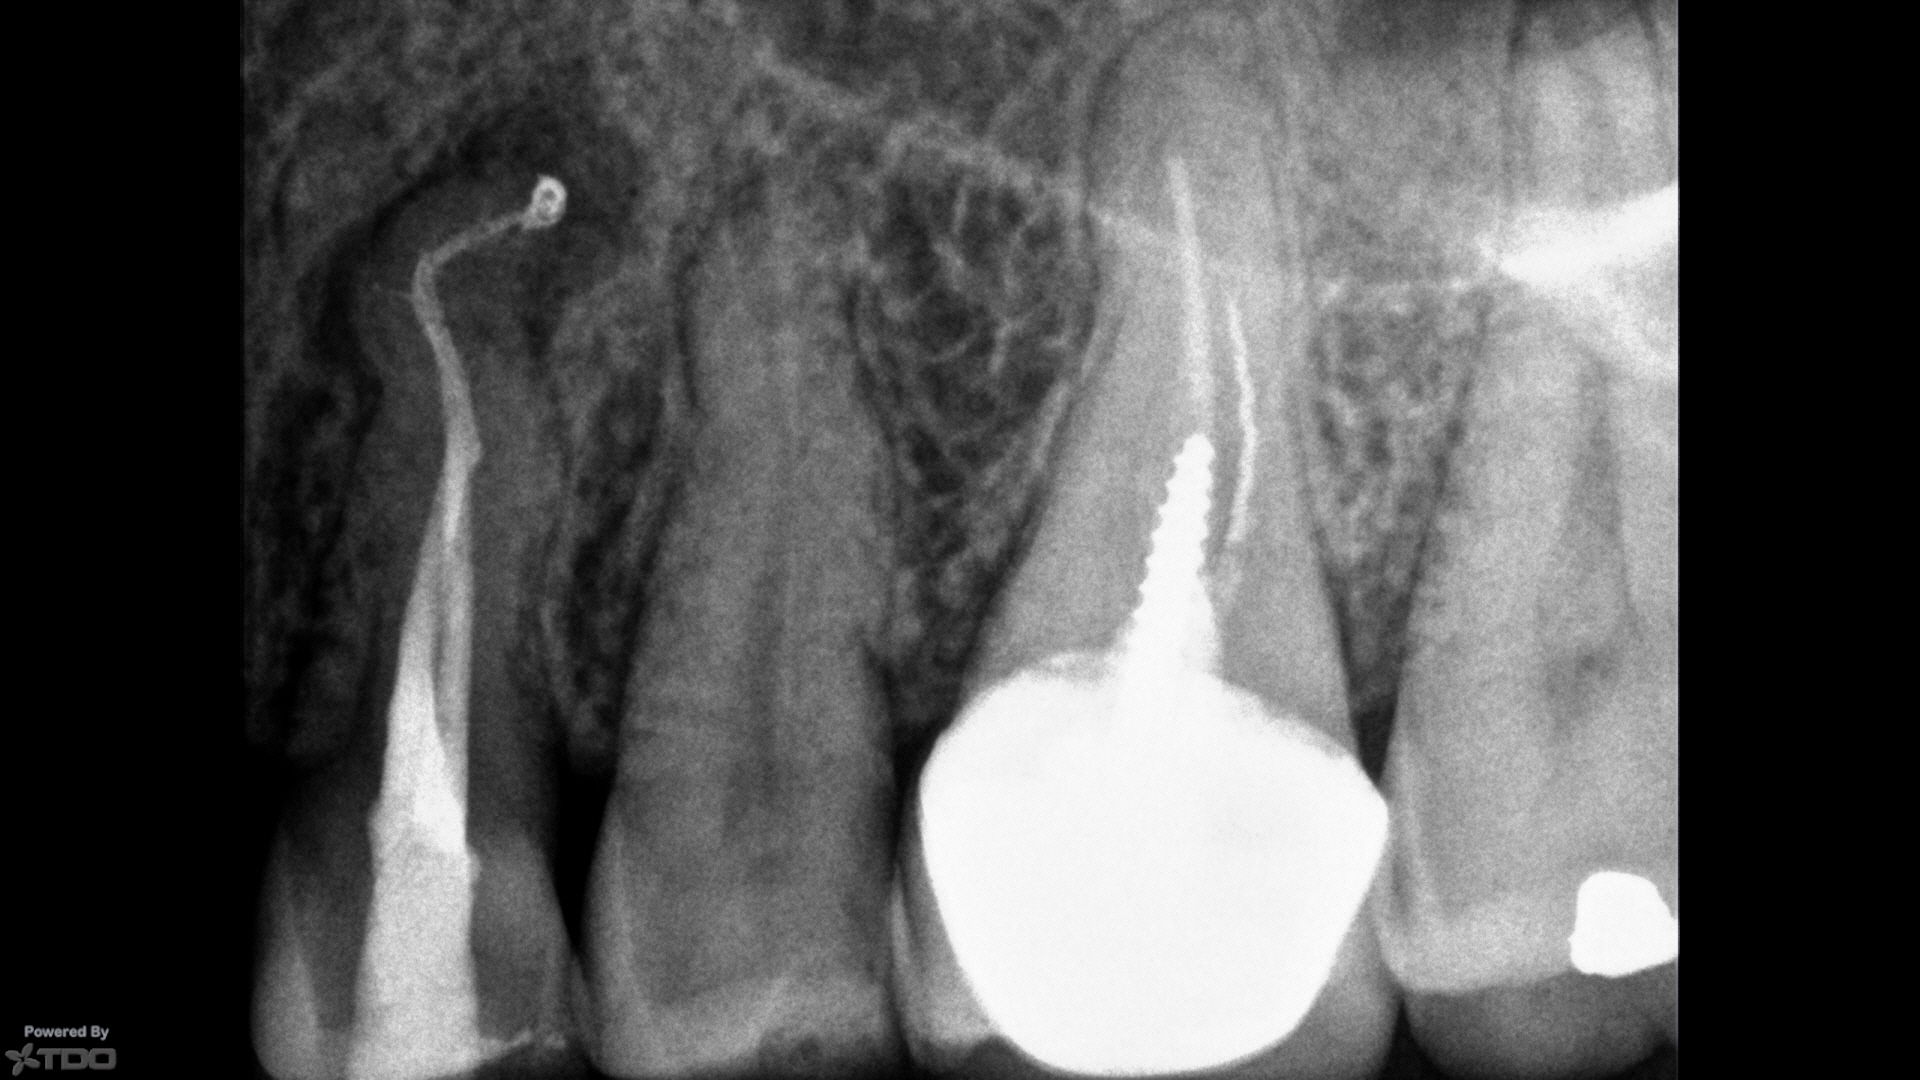

L'endodontie

Le savoir-faire du Dr Eve LAURENT inclut les traitements et retraitements endodontiques, la microchirurgie et la traumatologie.